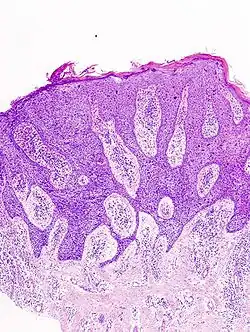

In situ disease

Bowen's disease is essentially equivalent to and used interchangeably with SCC in situ, when not having invaded through the basement membrane.[33] Depending on source, it is classified as precancerous[34] or SCC in situ (technically cancerous but non-invasive).[35][36] In SCC in situ (Bowen's disease), atypical squamous cells proliferate through the whole thickness of the epidermis.[33] The entire tumor is confined to the epidermis and does not invade into the dermis.[33] The cells are often highly atypical under the microscope, and may in fact look more unusual than the cells of some invasive squamous cell carcinomas.[33]